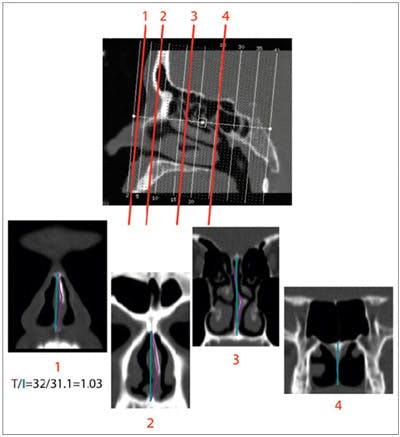

The CT and MRI images were imported into a Vitrea workstation (Vital Images; Minnetonka, Minn.). The images were measured with the ruler function. In the axial and sagittal views, images were centered on the midline. A point from anterior to posterior was chosen on the sagittal scan to serve as a reference point for the coronal measurements. The length of the septum was measured in the coronal plane from the cribriform plate superiorly to the hard palate inferiorly. Tortuosity was calculated by dividing the “actual” length of the septum by the “ideal” length, which was the length of a straight line from the starting point (superior aspect of the septum) to the ending point (inferior aspect of the septum). Septal deviation was measured at four different points along the cartilaginous and bony septum. The actual length and the ideal length were each measured at the piriform aperture, at the choanae, at half the distance from the tip of the nose to the piriform aperture, and at half the distance from the piriform aperture to the choanae (figure). The point of maximum tortuosity was used in defining the degree of septal deviation in each patient.

Figure. Tortuosity is measured at four precise points along the length of the nasal septum. Tortuosity is quantified as the ratio of the actual length of the septum (T) to the ideal length (I)-that is, T/I = Ratio. In this particular case, T had a value of 32 and I had a value of 31.1, yielding a ratio of 1.03. In the four images along the bottom, the purple lines represent the actual length (T) and the blue lines represent the ideal length (I).